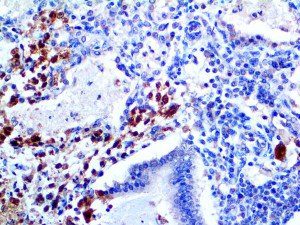

It is the ICU physician who is most likely to witness one of the deadliest manifestations of the abnormal immunological response, the cytokine storm syndrome (CSS). This response is also referred to by some as the cytokine release syndrome (CRS). CSS is characterized by continuous activation and expansion of macrophage and lymphocyte populations, which secrete large amounts of cytokines, causing the cytokine storm. This massive cytokine release is akin to hemophagocytic lymphohistiocytosis (HLH) disease, a syndrome characterized by initial unchecked and persistent activation of cytotoxic T lymphocytes and NK cells.

Clinical and laboratory manifestations of HLH include fever, enlarged liver and/or spleen, neurologic dysfunction, coagulopathy, liver dysfunction, cytopenias (i.e., low levels of erythrocytes, leukocytes, and/or platelets), hypertriglyceridemia, hyperferritinemia, hemophagocytosis, and eventually diminished NK cell activity as the immune system becomes progressively paralyzed. HLH can be familial (primary HLH) or secondary to another disease process (sHLH), such as rheumatic disease, in which it is referred to as macrophage activation syndrome (MAS, characterized by elevated ferritin).